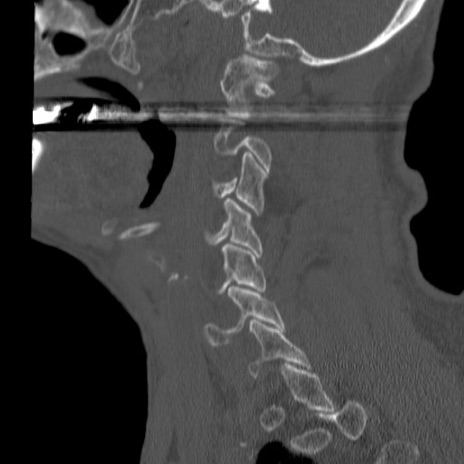

症例46 頚椎CT(矢状断像)

【症例】80歳代男性

【主訴】両側頚部〜上肢のしびれ

【現病歴】昨日、自宅内で転倒、その後より上記症状あり。意識障害なし。

【身体所見】両側上肢のallodynia(熱痛覚過敏)あり。MMTおよびDTRは正確な所見取れず。両上肢の挙上はなんとか可能。

異常所見と診断は?